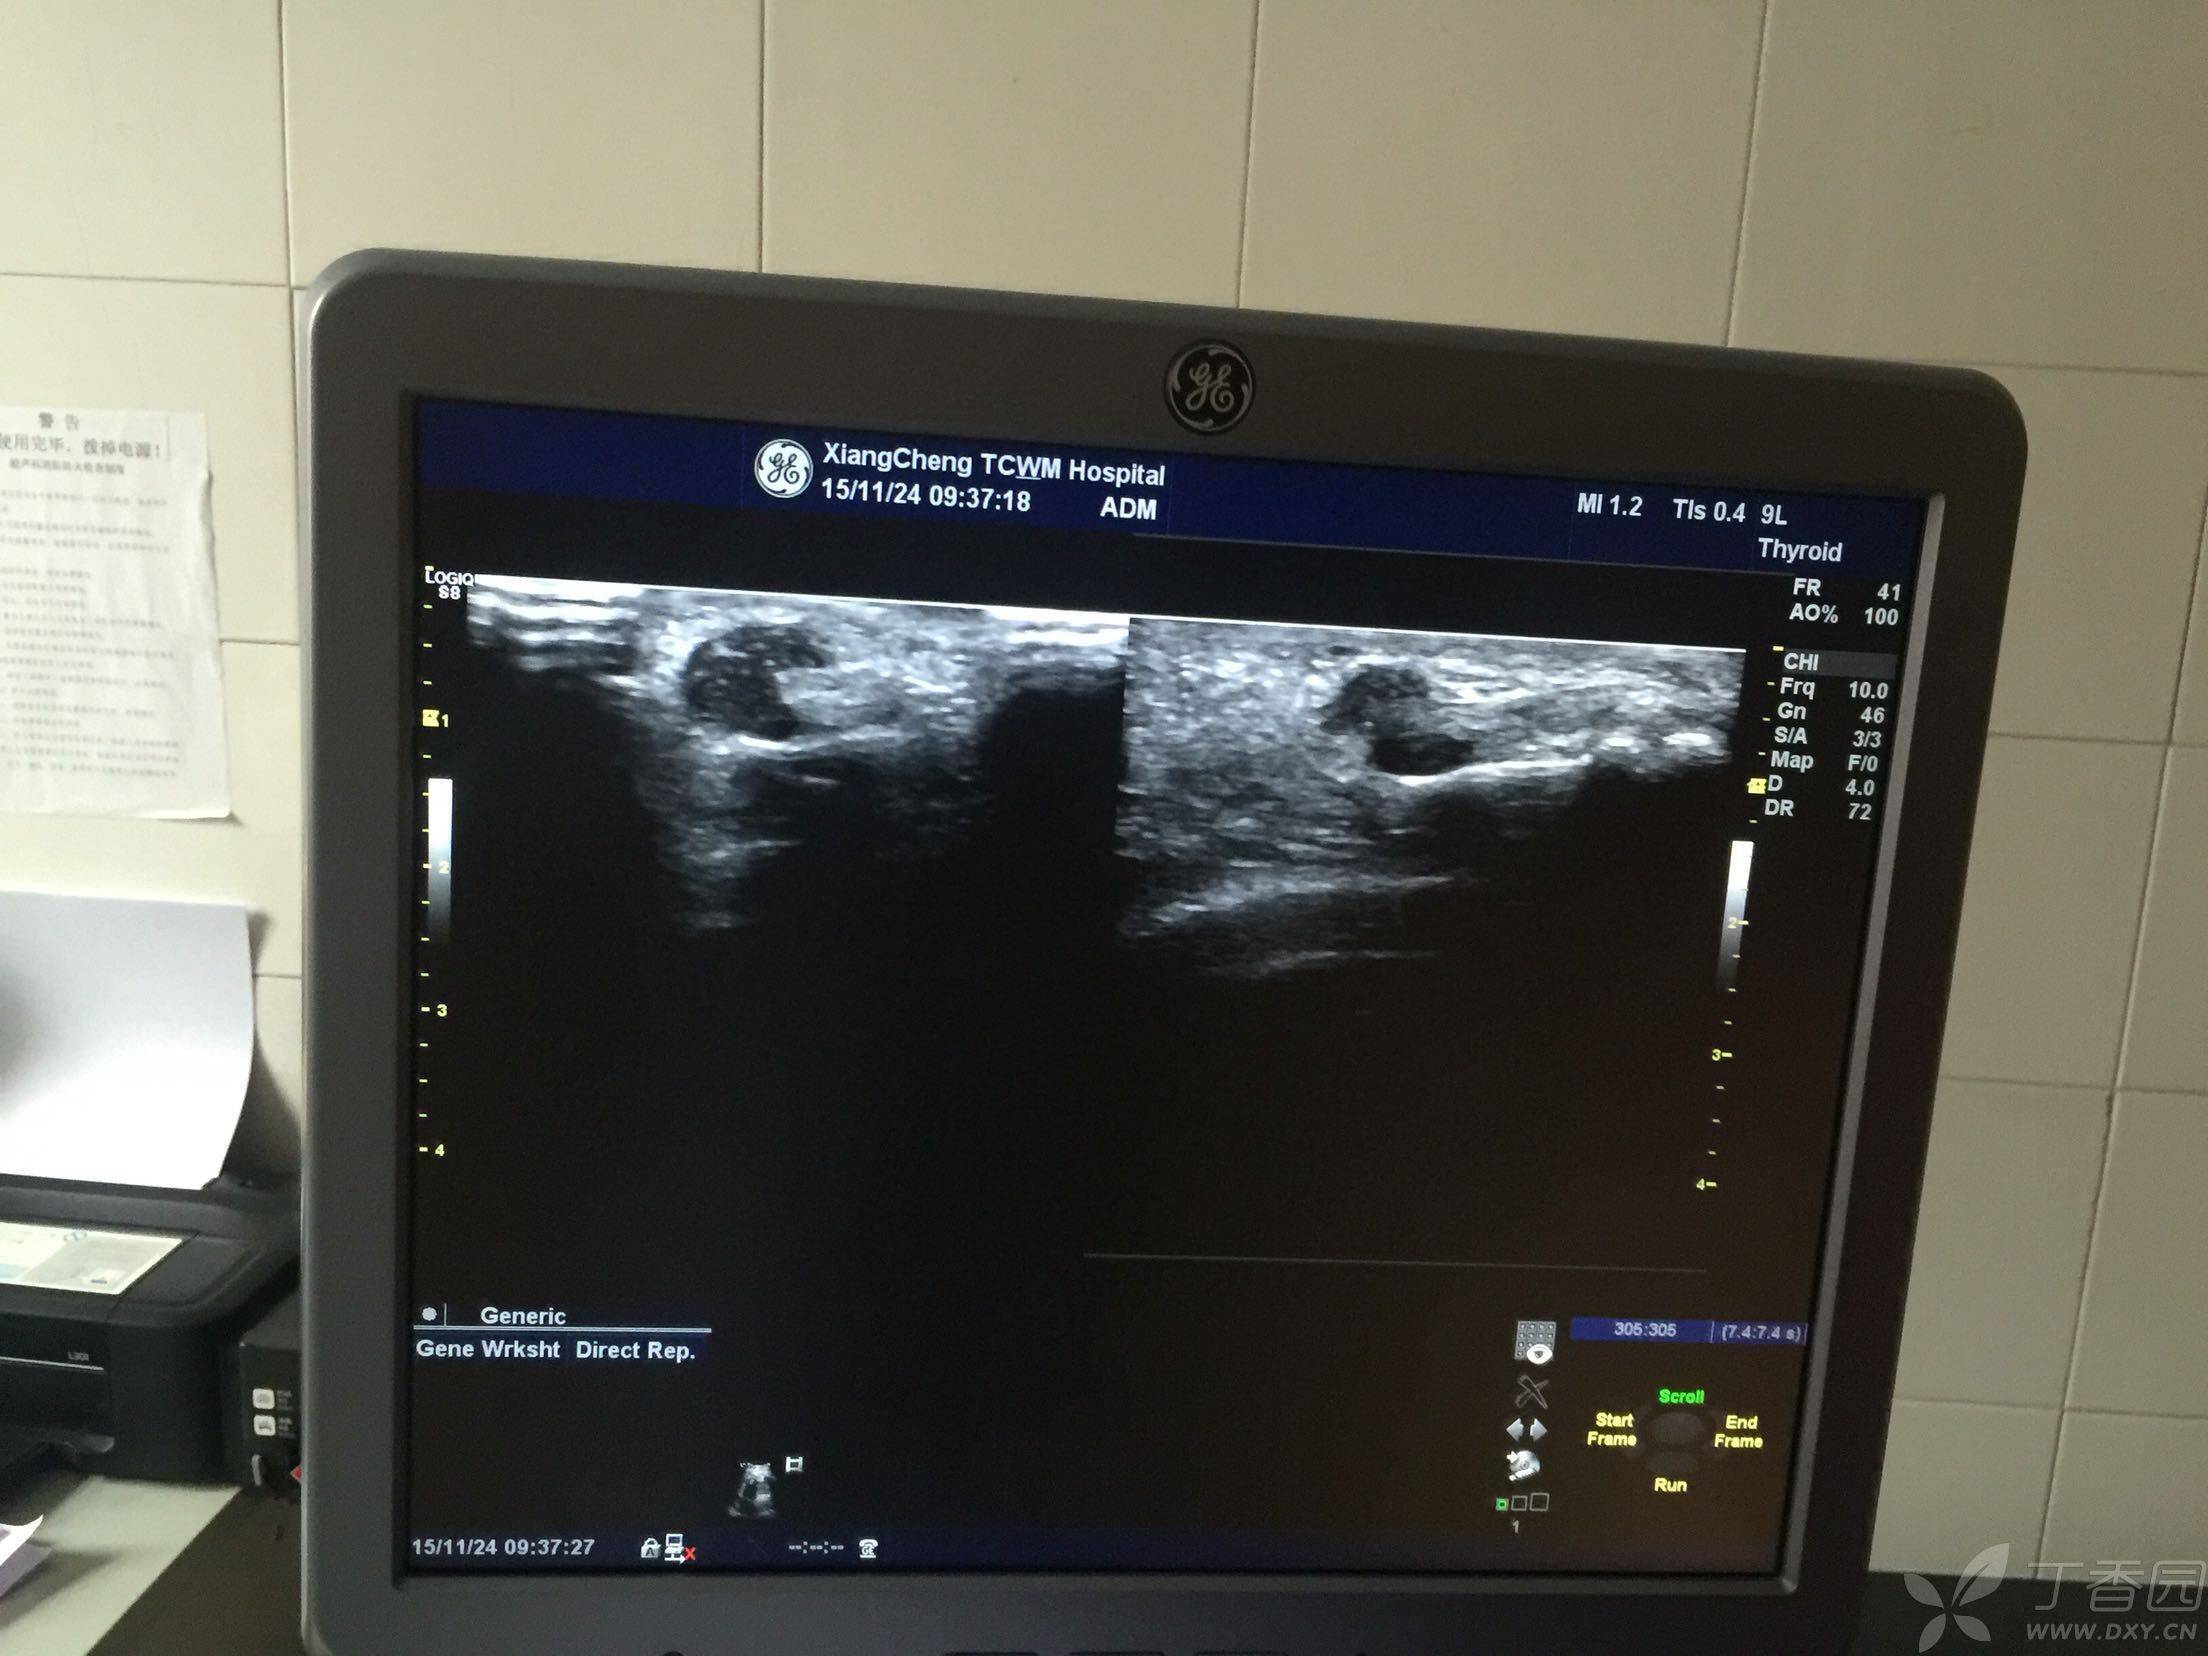

低回声结节是影像学检查中对病变部位的一种描述在超声等影像学检查中,医生会根据组织或病变部位对声波的反射程度,将其回声特征分为高回声低回声等回声和无回声等类型低回声结节指的是该病变部位的密度低于周围正常组织的密度,在超声图像上呈现为较暗的区域这种表现通常提示病变组织内部结构与。

乳腺低回声结节是超声检查中发现的乳腺组织内异常低回声区域,提示可能存在病变,但需进一步检查明确性质具体含义在乳腺超声检查中,正常乳腺组织会呈现均匀的中等回声若发现局部区域回声低于周围组织即“低回声”,则提示该区域可能存在结构异常这种低回声表现可能是实性肿块囊性病变或混合性病变。